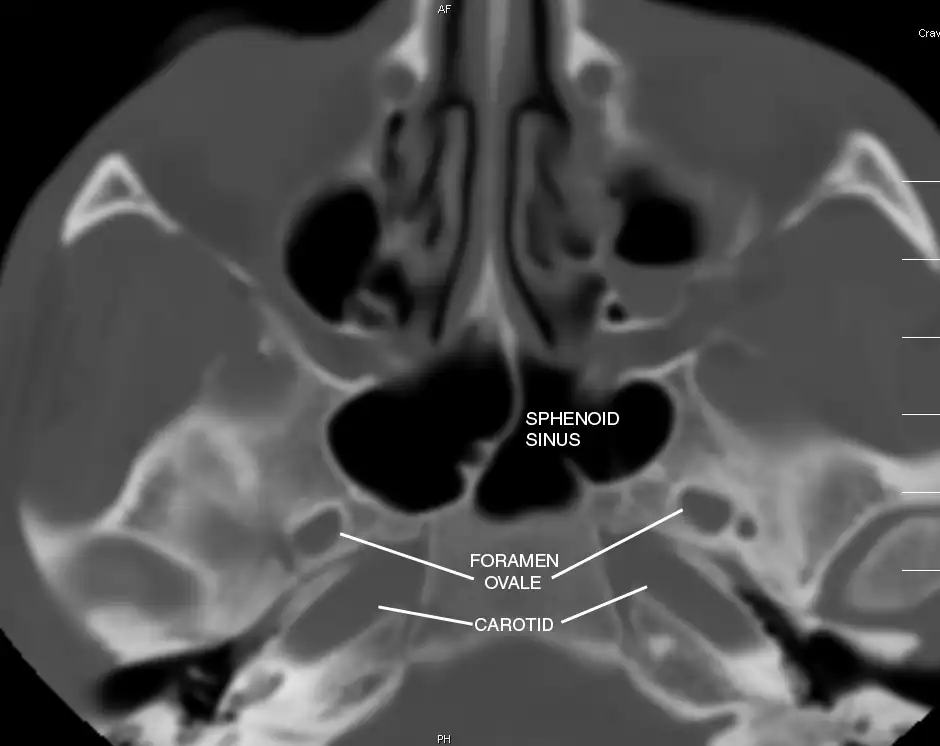

Sphenoid Sinus has 12 close structures: II, III, IV, V1, V2, VI, Vidian Nerve, Carotid artery, Brain, Dura, Pituitary.

Pertinent Sinonasal Anatomy

V2 = Maxillary division, Trigeminal Nerve: exits foramen rotundum, superomedial to V3's foramen ovale.

C = Carotid Artery: often with bony dehiscence into sphenoid. Together with CN II forms opticocarotid recess.

Sinus communicates posteriorly, so thrombosis is bilateral.